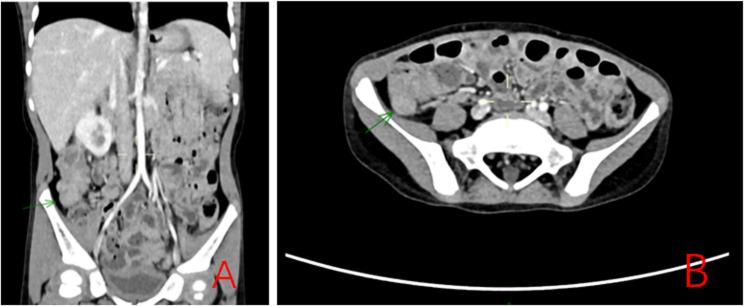

A 5-year-old male presented with paroxysmal periumbilical abdominal pain and persistent hypokalemia (2.72 mmol/L). Imaging revealed a 4 cm × 3 cm × 3 cm ileocecal mass, initially suspected as lymphoma. Colonoscopy identified a pedunculated polyp, excised via electrocoagulation. Histopathology confirmed a juvenile polyp. Genetic testing identified compound heterozygous mutations in the SLC12A3 gene (paternally inherited c.923dup and maternally inherited c.2521 + 253 C > T),confirming GS. Postoperative potassium supplementation stabilized serum potassium (3.27 mmol/L at discharge).

一名5岁男性出现阵发性脐周腹痛和持续性低钾血症(2.72 mmol/L)。影像学检查发现一个4 cm×3 cm×3 cm的回盲部肿物,最初怀疑为淋巴瘤。结肠镜检查发现一个带蒂息肉,通过电凝切除。组织病理学证实为幼年性息肉。基因检测确定SLC12A3基因存在复合杂合突变(父系遗传的c.923dup和母系遗传的c.2521+253 C>T),确诊为GS。术后补钾使血清钾稳定(出院时为3.27 mmol/L)。